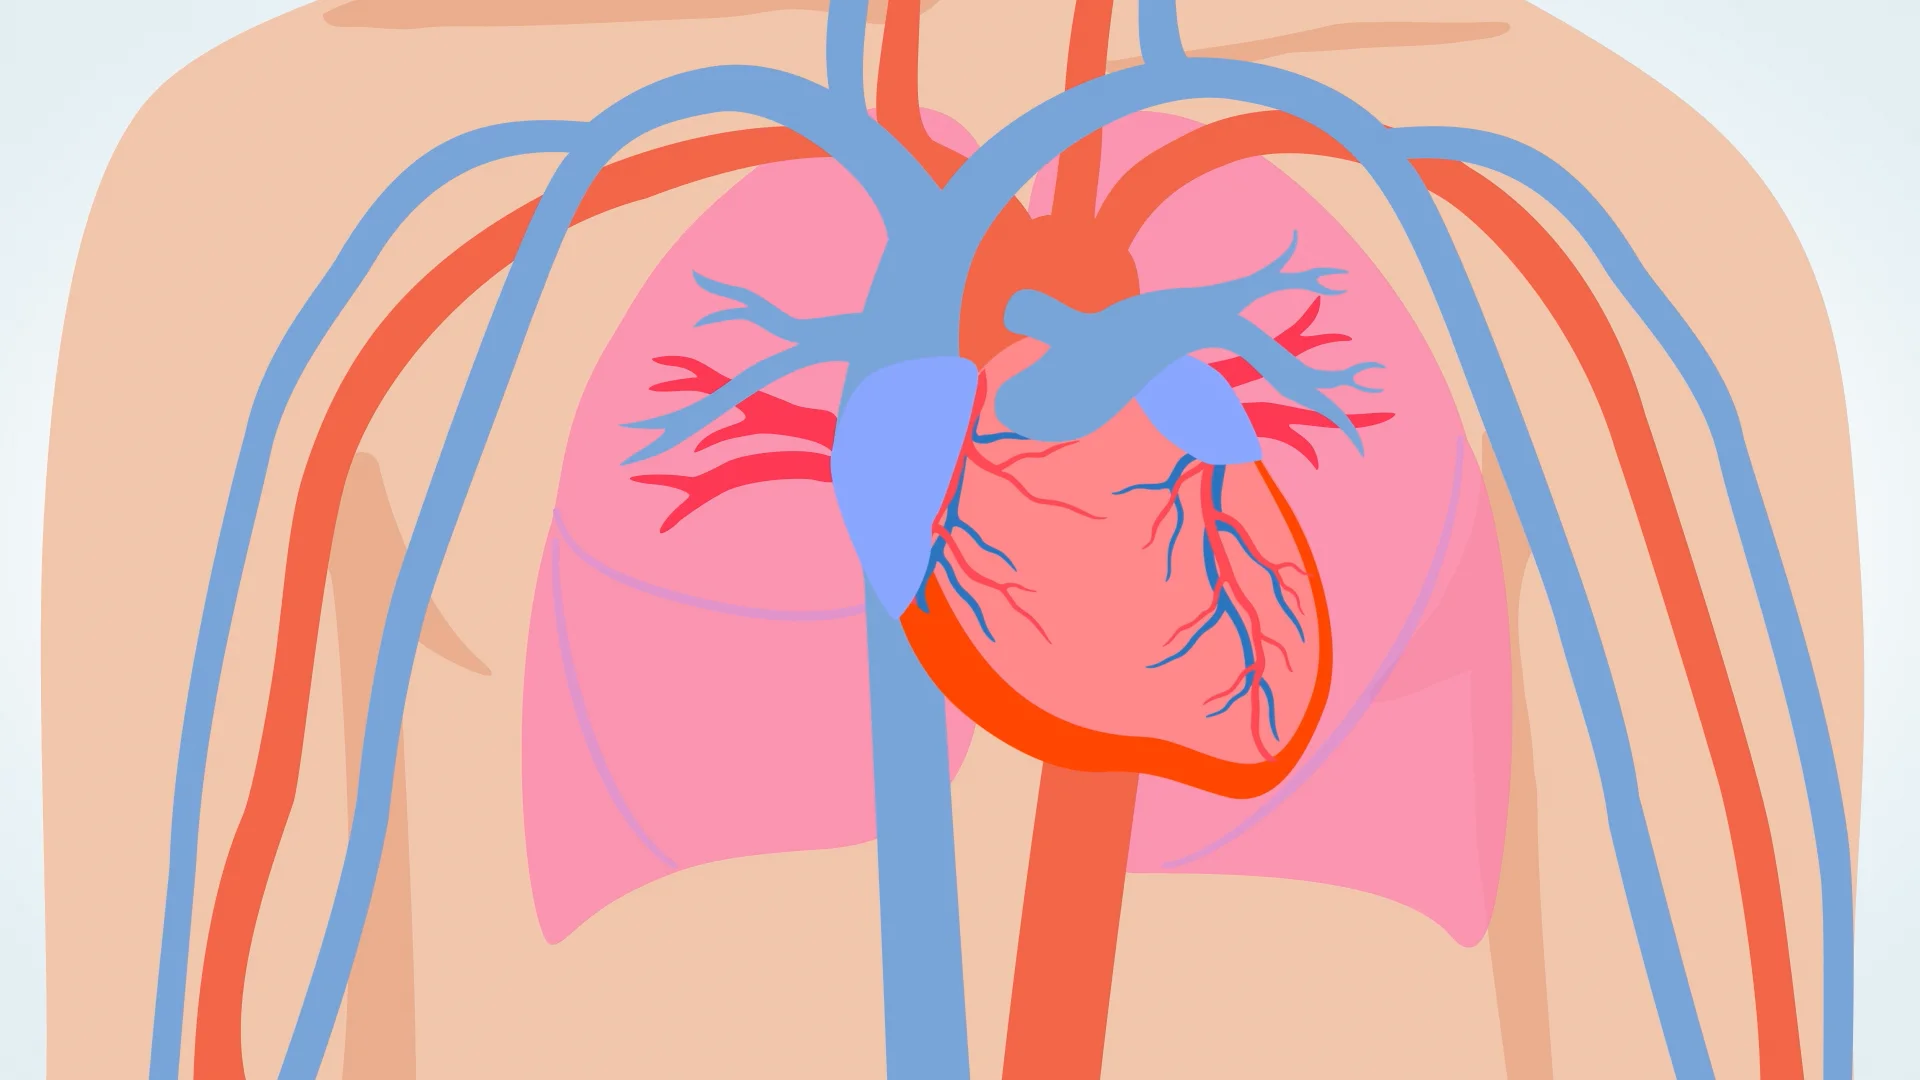

Entre todos los órganos del cuerpo humano, hay uno que representa la constancia silenciosa, el ritmo inquebrantable de la vida: el corazón. Este órgano muscular, del tamaño aproximado de un puño cerrado, late sin descanso desde antes del nacimiento hasta el último instante de vida. Si se detiene, todo lo demás también lo hace. Por eso, no es exagerado decir que en cada uno de sus latidos se encuentra contenida la promesa de seguir vivos.

Todo este esfuerzo impulsa la sangre a través de una red de más de 100,000 kilómetros de vasos sanguíneos, lo suficiente para dar más de dos vueltas al planeta Tierra. Esa sangre lleva oxígeno y nutrientes a cada célula del cuerpo, recoge los desechos metabólicos y los lleva a ser filtrados. Y todo esto ocurre gracias a un solo órgano que nunca descansa por completo.

La coordinación del latido cardíaco está a cargo del nódulo sinoauricular, conocido como el marcapasos natural del corazón. Desde ahí, una señal eléctrica recorre el miocardio y marca el ritmo entre contracción y relajación. Es un proceso tan perfecto que solo notamos su falla cuando aparece la enfermedad.

Aunque el corazón pesa solo entre 250 y 350 gramos, genera suficiente presión para que la sangre llegue desde la cabeza hasta los pies. Y lo hace más de 100 mil veces al día, sin que le demos las gracias. Quizás ha llegado el momento de hacerlo.